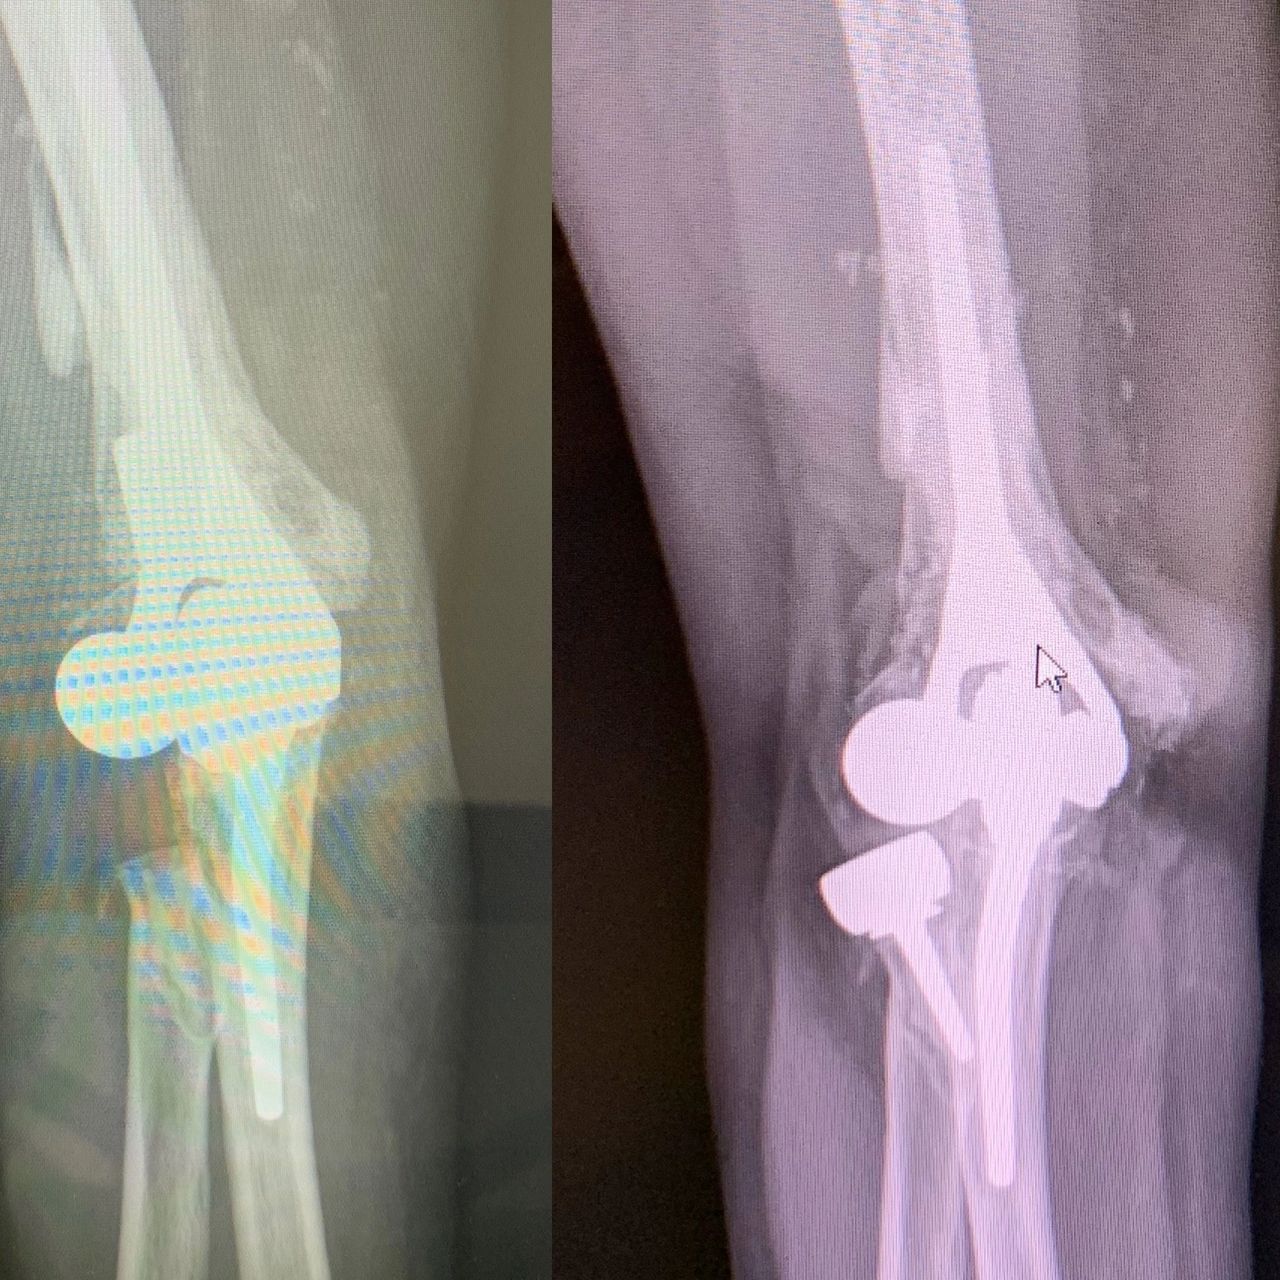

The physical activities were a comedy of errors and a learning curve to do anything. I am surprised I wasn’t admitted to a padded room. The limitations of both arms, the right arm worse each day with the double duty required to use while the other arm healed. Too much time with no hands had my nose into the computer doing extensive online research; I read a few great articles written by a top orthopedic elbow surgeon at the Mayo Clinic in Rochester. Ironically, my insurance was in-network there. I emailed a detailed summary of my medical records to Dr. Shawn O’Driscoll. He responded immediately. We did a zoom meeting to further discuss if he could help. We agreed to further the evaluation in person. He determined the artificial prosthetic had loosened, and the radial attachment had shifted out of place. My surgery was scheduled for October 30th, 2019, for a revised total elbow replacement with exploratory of the ulnar nerve.

On surgery day, I was a tad under the weather. My body was still adapting and adjusting after nine years of opioids and cocktails of medications. I was mentally prepared for surgery as I felt my body’s challenge was also from the pain. Dr. O’Driscoll performed the surgery; he replaced the elbow component and elected to leave out the radial head component. In his experience, the revised radial head on a revised total elbow has complications and a low success rate. The ulnar nerve was a zig-zag, impossible to distinguish, which added to his decision. The hope was the soft tissue would support the radial bone. He expressed guarded optimism about my prognosis.

I flew home two days later in an enormous heavy surgical cast, fixed straight and as big as my leg. I established a good relationship with my hand surgeon instead of flying back to Rochester for my 2-week post-op. Dr. Chan agreed to take the x-rays and remove the cast and sutures for Dr. O’Driscoll. At the same appointment, we discussed the removal of the wrist hardware. The friction of the metal was causing irritation to a tendon that made my middle finger stick, called a trigger finger. He injected a steroid for the inflammation. The surgery would be scheduled at a future date to allow the other arm to heal. One hand at a time.